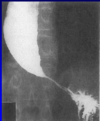

מהו הממצא

אכלאזיה וושט מורחבת עם מקור הציפור